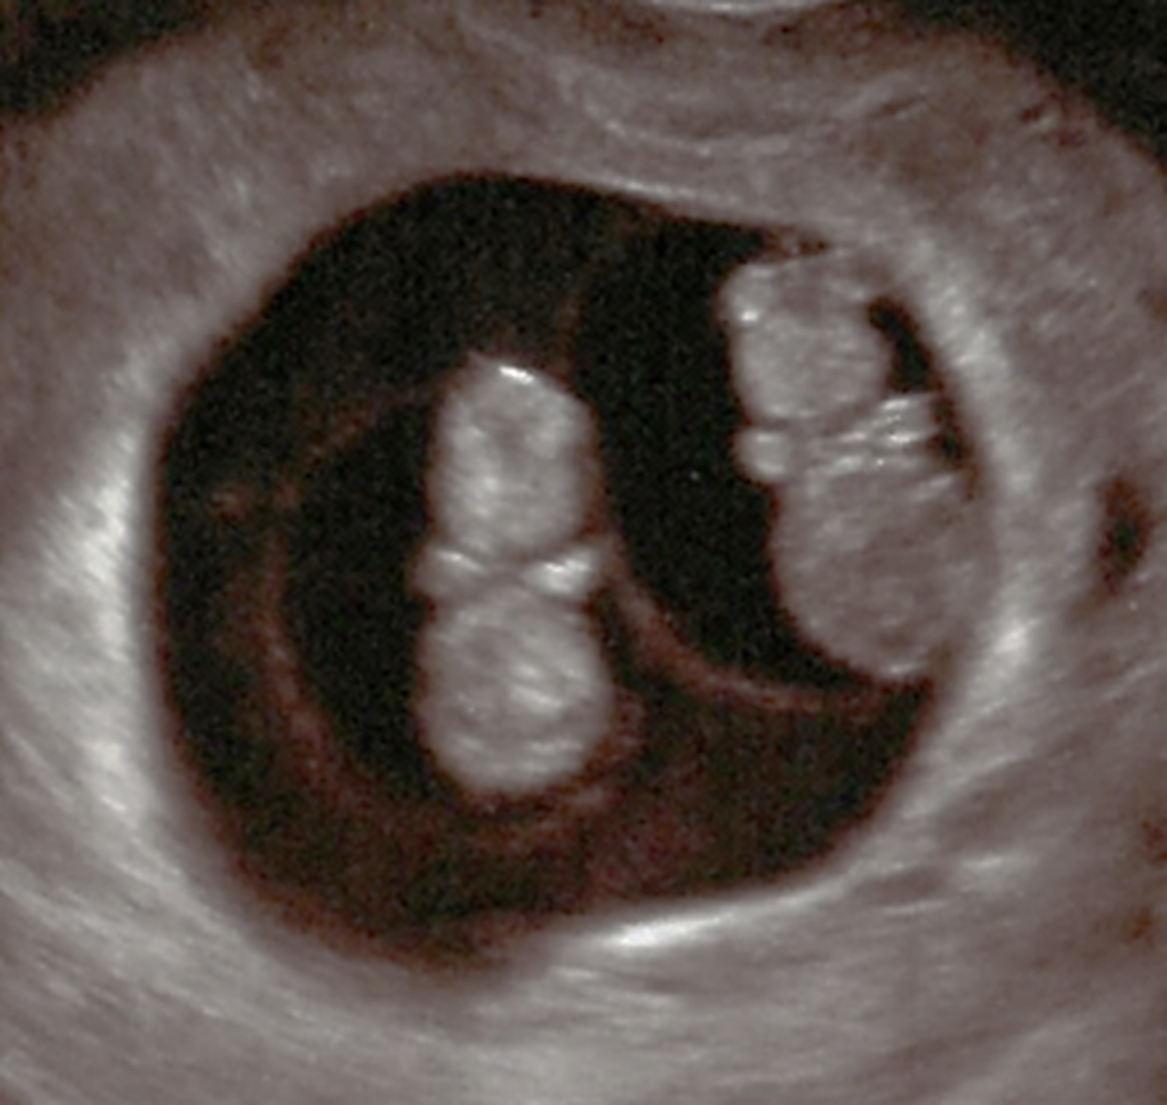

A 30-year-old primipara who conceived spontaneously was diagnosed with a monochorionic (MC) diamniotic twin pregnancy through ultrasonographic findings at 9 weeks’ gestation because there were two fetuses. They were in a common gestational sac, and each had its own amniotic cavity. The primipara was referred to us at 12 weeks’ gestation for the management of her twin pregnancy. At 26 weeks, serial scans showed that the fetuses had a different sex. No abnormalities were found in their anatomy, including the genital organs. The twins were delivered via cesarean section at 38 weeks’ gestation. Apgar scores and pH values were normal. Twin A was a phenotypically normal female, with a birth weight of 2612 g, and Twin B was a phenotypically normal male, weighing 2458 g. Histological examination of the placenta confirmed MC diamniotic twinning (see Figures 1 and 2). Karyotyping was performed on each umbilical cord blood and revealed the chimeric karyotypes 46,XX[15]/46,XY[15] and 46,XY[21]/46,XX[9] for Twin A and Twin B, respectively. Ultrasonography determined normal female and male internal genitalia concordant with their phenotypes (see Figures 3 and 4). Karyotyping was performed again from blood samples at 7 months of age. The results confirmed that the twins had similar chimericg karyotypes: 46,XY[7]/46,XX[13] in Twin A and 46,XX[9]/46,XY[11] in Twin B.

Fig. 4. Ultrasound findings for Twin B. A normal penis (male reproductive organ) could be seen indicating that Twin B is a boy.

To determine whether this chimerism was temporarily due to vascular communication via placenta between twins or permanently due to the chimera of hematopoietic stem cells, karyotype analysis was repeated. At 1-year-old, we evaluated their buccal swab cells. The results were normal female and normal male karyotypes, respectively — 46,XX[98]/46,XY[2] in Twin A and 46,XY[98]/46,XX[2] in Twin B. Furthermore, ultrasonography revealed normal female and male internal genitalia. These results showed that they were MC dizygotic (DZ) twins (MC-DZ twins). Two years later, the twins underwent blood typing tests. ABO blood grouping was carried out using the manual tile method using anti-A, -B and -AB antisera, along with the micro-column agglutination technique. In addition, because of the possibility of chimerism in the blood group type, the blood sample was analyzed using the transferase method as well as flow cytometry. These revealed a very subtle blood group chimerism that would be overlooked without chromosomal information (Table 1). At first glance, the blood of Twin A was B type, but ABO glycosyltransferase examination revealed that the blood was in fact O type. It was inferred that this was the reason flow cytometry revealed the blood of Twin A to be a type B/O chimera.